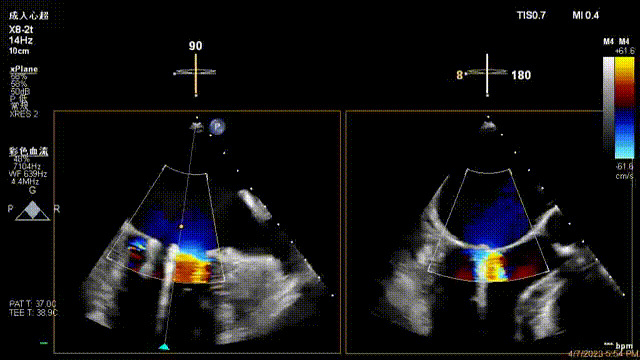

接受治療的是一例器質(zhì)性重度二尖瓣反流(DMR)患者,主訴“反復(fù)活動后胸悶,氣促3年余”。術(shù)前超聲顯示,雙房增大,二尖瓣脫垂伴重度反流,輕度三尖瓣反流,輕度肺高壓,升主動脈增寬。手術(shù)經(jīng)股靜脈-房間隔入路,采用全身麻醉插管,在TEE和DSA引導(dǎo)下完成房間隔穿刺。置入JensClip瓣膜夾系統(tǒng)后,在左房調(diào)整瓣膜夾的位置和軸向,后進(jìn)入左室,在TEE引導(dǎo)下捕捉二尖瓣前后瓣葉,并關(guān)閉瓣膜夾。經(jīng)TEE反復(fù)確認(rèn)手術(shù)效果后最終鎖定并釋放瓣膜夾。術(shù)后即刻超聲顯示瓣膜夾位置穩(wěn)定,功能良好,術(shù)前二尖瓣反流4+,術(shù)后0反流,肺靜脈逆流和左房壓都顯著好轉(zhuǎn),手術(shù)圓滿成功(以上數(shù)據(jù)都來源于醫(yī)院的臨床記錄)。術(shù)后患者狀態(tài)良好,目前已安排出院。

術(shù)后超聲顯示二尖瓣反流消失,瓣膜夾穩(wěn)定